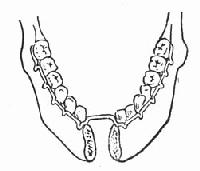

(2)粉碎性骨折或骨缺损:清创关闭口腔穿通伤后,由于骨缺损不能做骨间固定者,可使用特制的唇弓夹板,先行单颌结扎,保持其正常的颌弓(图88-13),再行颌间结扎,恢复其咬合关系,并利用上颌固定下颌。此外,在有条件的情况下,可在骨缺损区两断端间植入不锈钢夹板,两端各有两颗螺旋钉固定,恢复正常颌弓和咬合关系。两者均可在后期行植骨术修复骨缺损。

图88-13 下颌骨粉碎性骨折可用唇弓夹板固定